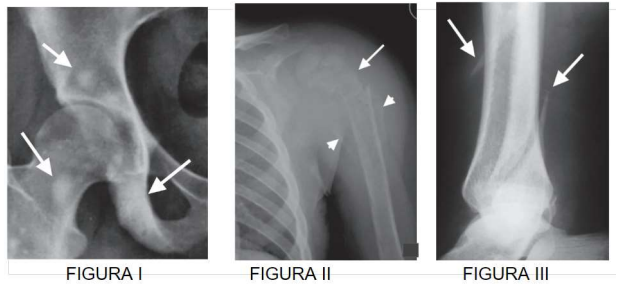

Analise as figuras (I, II e III) e as indicações das setas, depois assinale a alternativa correta.

Figura I: Fêmur e quadril; Figura II: Úmero; Figura III: Tíbia e Fíbula.

Figura I: Fêmur e quadril; Figura II: Clavícula; Figura III: Tíbia e Fíbula.

Figura I: Fêmur e quadril; Figura II: Escápula; Figura III: Tíbia e Fíbula.

Figura I: Quadril e Pelve; Figura II: Úmero; Figura III: Fêmur.